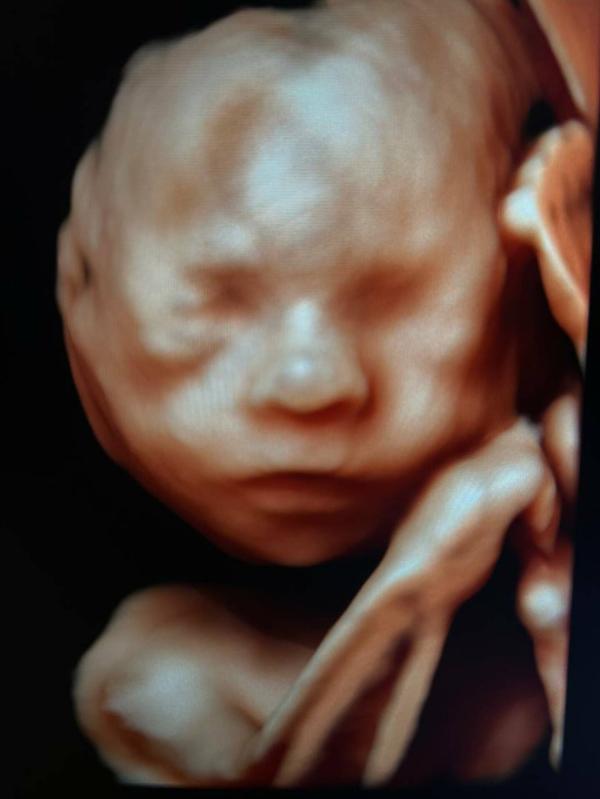

"Как часто я ошибаюсь с полом на первом скрининге?"

Если исключить те моменты ,когда половой бугорок невозможно четко вывести из-за различных причин которые я обычно озвучиваю во время исследования (фиксированное положение плода, гипертонус , высокий ИМТ , срок менее 13 недель по КТР...)

В среднем не более 2-3 РАЗ В ГОД .